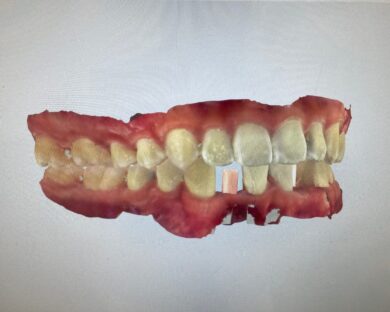

インビザラインの治療計画では、下顎前歯がより美しく審美的に並ぶよう、ご自身の歯とインプラントの歯がほぼ同じ幅径になるよう計算し配列を行いました。

インプラントは世界シェアNo,1の「ストローマン」インプラントを採用。若年者の方も安心して長期的にお使いできるよう配慮しています。

• インビザライン終了後、インプラント2本埋入2週間後

• 治療後